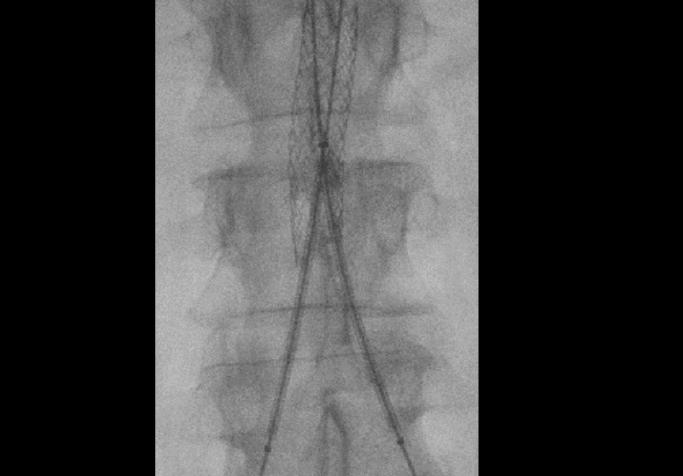

Seu tempo na sala de cirurgia é um recurso inestimável. Obter imagens precisas no momento certo, minimizar a exposição à radiação e manter um fluxo de trabalho estável não são vantagens; são essenciais.

Em procedimentos minimamente invasivos, onde a anatomia pode mudar a cada movimento e as decisões precisam ser tomadas instantaneamente, a capacidade de trabalhar com segurança, rapidez e confiança faz a diferença entre um procedimento eficiente e um repleto de imprevistos.